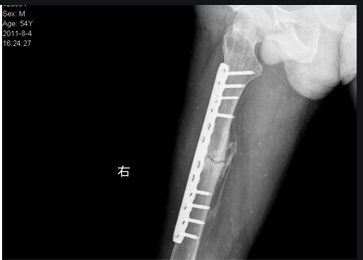

民政部國(guó)家康復(fù)醫(yī)院骨一科焦紹鋒主任團(tuán)隊(duì)“醫(yī)生,您好,我小腿骨折1年半了,在我們當(dāng)?shù)蒯t(yī)院做過(guò)兩次手術(shù)了,可是骨折那還是沒(méi)長(zhǎng)上,也做過(guò)各種治療,走路還是疼痛,在家里也干不了活,不能照顧家里,也上不了班,特別著急,晚上失眠!體重降低了很多,找不少醫(yī)生看過(guò),說(shuō)還需要做手術(shù)?您這里有什么好辦法嗎?能治好嗎?”,經(jīng)常遇到患者心情沮喪且沒(méi)有信心的來(lái)門診看這種病,那我們談?wù)勥@個(gè)病是什么病、怎么得的?怎么治療效果好?1、定義:骨折不愈合通常稱為骨不連,指骨折端愈合功能停止,甚至骨折端形成假關(guān)節(jié),其病理特征是骨折兩端僅以軟骨或纖維組織相連,骨不連是骨科的疑難疾病之一。2、骨不連分類:根據(jù)骨折端活力情況,分為2種類型。第一種為血管豐富肥大型:骨折端富有生命力,產(chǎn)生明顯的生物學(xué)效應(yīng),又分為幾種壓型:象足型骨不連,馬蹄形骨不連,營(yíng)養(yǎng)不良型骨不連。第二種骨不連為缺血萎縮型:骨折端缺乏活力,生物學(xué)反應(yīng)少。3、治療:方法多,因人而異,個(gè)性化選擇!3.1非手術(shù)治療包括輔助外固定、高能震波、電磁波刺激、沖擊波治療等。3.2手術(shù)治療:包括改善局部生物學(xué)環(huán)境和加強(qiáng)局部機(jī)械穩(wěn)定性。改善生物學(xué)環(huán)境包括:去除感染灶、骨移植、應(yīng)用Ilizarov技術(shù)。加強(qiáng)機(jī)械穩(wěn)定性方法包括加強(qiáng)內(nèi)固定和外固定方法。4、Ilizarov技術(shù):微創(chuàng),早期負(fù)重,功能鍛煉,恢復(fù)快!應(yīng)用Ilizarov技術(shù)治療骨不連,去除原有內(nèi)固定術(shù)后,僅安裝外固定架,術(shù)后依靠調(diào)整外固定架行斷端畸形矯正,并可行斷端加壓或局部加壓-牽引(手風(fēng)琴技術(shù))治療骨不連,且斷端無(wú)需行自體髂骨或異體骨植骨術(shù),減小創(chuàng)傷和經(jīng)濟(jì)負(fù)擔(dān),患者可早期下地負(fù)重行走,臨床治療效果滿意。前蘇聯(lián)Ilizarov教授于20世紀(jì)50年代末60年代初,根據(jù)大量臨床和實(shí)驗(yàn)研究提出張力-應(yīng)力法則,即給活體組織持續(xù)、穩(wěn)定的緩慢牽伸產(chǎn)生一定張力,可刺激組織的再生和活躍生長(zhǎng),其生長(zhǎng)方式類似胎兒組織的細(xì)胞分裂,設(shè)計(jì)出了全環(huán)式金屬外固定支架,環(huán)與環(huán)之間通過(guò)螺紋桿連接,通過(guò)調(diào)整螺紋桿改變肢體長(zhǎng)度和角度,成為了矯正肢體“變形”及肢體延長(zhǎng)術(shù)的利器,治愈大量應(yīng)用常規(guī)方法難以治療的疾病,引起世界廣泛關(guān)注及應(yīng)用。局部加壓-牽引(手風(fēng)琴技術(shù)):治療骨不連,類似于演奏手風(fēng)琴,在骨不愈合部位上下各有兩個(gè)環(huán)。A治療開始前,疤痕組織填充骨段之間的間隙。B第一階段,壓縮,使骨段接觸并壓碎疤痕組織。C,第二階段,開始牽張,由壓碎的疤痕組織和骨表面產(chǎn)生纖維血管組織柱。在新形成的組織和在擠壓中幸存下來(lái)的舊組織之間存在不同程度的平衡。D,如果再生發(fā)育的強(qiáng)度沒(méi)有跟隨牽張,那么第三階段,重復(fù)非常緩慢的壓縮,有助于刺激組織向性,使新舊組織之間的平衡向積極的方面發(fā)展。E第四階段,重復(fù)牽張,幫助膠原束在骨基質(zhì)中鞏固并刺激產(chǎn)生成骨細(xì)胞。在X線片上可以看到,最初的再生云具有縱向的鈣化柱。我科已應(yīng)用手風(fēng)琴技術(shù)治療多例下肢股骨、脛骨骨不連患者,術(shù)中均未植骨,創(chuàng)傷小,治療效果滿意。典型病例見(jiàn)下圖:男,52歲,外傷致右小腿骨折后引起骨不愈合,骨不連20年、原內(nèi)固定鋼板斷裂,在我科實(shí)施內(nèi)固定物取出、ILizarov外固定架矯形術(shù),矯正畸形,應(yīng)用骨折端加壓-牽拉技術(shù),術(shù)后18個(gè)月,骨折端順利愈合